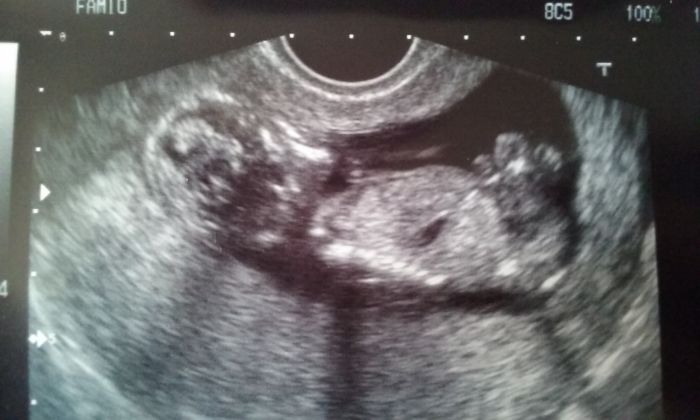

Hlásím hlásím. .. živé a zdravé mrně sebou pěkně mrskalo... a nohy má tedy dlouhé předlouhé

Petko..veliká gratulace a krásná fotecka..Vlasti myslím že Pětka na screening ani nejde ze ..